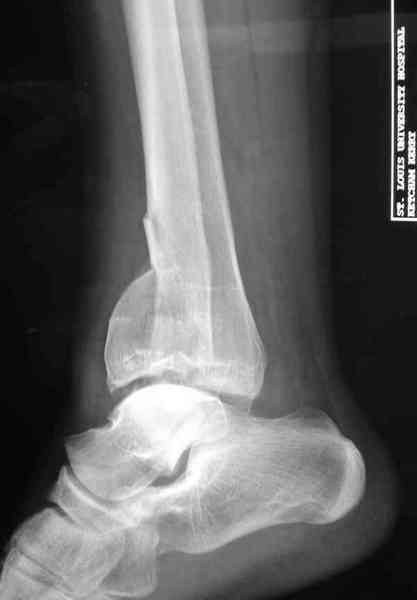

Переломы пилона сопровождаются ударом со сминанием в метафизарной части большеберцовой, то есть со значительной потерей костного объема.

При репозиции суставных поверхностей образуются полости в метафизарных отделах, без заполнения их

структуральными элементами невозможно предохраниться от посттравматической деформации. Латеральная колонна удерживается малоберцовой поэтому голень деформируется в варус.

Здесь выставлена пара случаев перелома пилона, оба

случая леченные этапным наружным фиксатором.

Второй случай фиксирован аппаратом Илизарова.